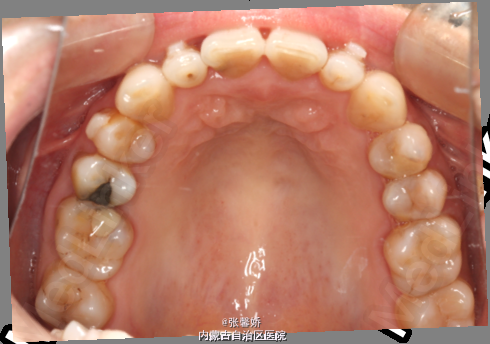

上中线右偏1mm,A2、D4反合,A2、B2畸形牙偏小,拥挤度上颌4mm、下颌6mm。Spee曲线:左侧3mm,右侧2.5mm

牙列中度拥挤;A2、D4反合 处理:时代天使隐形矫治器矫治 拔除C8、D8 适当下前牙邻面去釉 排齐整平上下牙列,改正A2、D4反合 治疗时间2年左右,矫治后牙齿排列整齐,咬合关系良好,患者满意。

一年后随访,患者咬合关系仍稳定,尖窝锁结良好。 隐形矫治适应证的选择很重要,适合中低难度的成人病例,患者的配合和依从性要求较高。 此患者术前全景片可见多个充填物,为龋易感患者,而且牙周也不是很好,隐形矫治没有拖槽更利于患者口腔卫生的维护,防止龋病的发生和牙周病的加重。